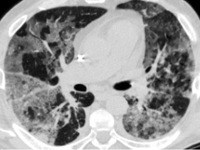

Функциональные дыхательные тесты выявляют нарушение вентиляции и расстройства диффузионной способности легких (при ИЛФ — рестриктивного типа с резким и крайне резким снижением легочных объемов). Рентгенологическими признаками интерстициальной пневмонии могут являться симметричные полупрозрачные затемнения по типу «матового стекла», в основном в нижних отделах легких; утолщение междолькового и внутридолькового интерстиция; кистозно-фиброзные изменения, периваскулярная и перибронхиальная инфильтрация и тракционные бронхоэктазы.

КТВР помогает уточнить распространенность поражения легочной ткани, оценить стадию, активность и темпы прогрессирования фиброзного процесса. Важным этапом диагностики интерстициальной пневмонии является биопсия легкого с гистологическим анализом биоптатов легочной ткани. ЭхоКГ-симптомы нарушения гемодинамики в малом круге кровообращения отмечаются только при достаточно высоких показателях площади фиброзных изменений в легких.

Компьютерная томография (КТ). Томография позволяет создать детальное изображение легких и прилегающих к ним структур. Интерстициальные заболевания легких, как правило, виды при КТ.

КТ с высоким разрешением. Особые настройки томографа при подозрении на заболевание интерстиция увеличивают эффективность диагностики.